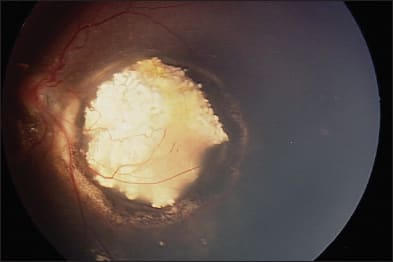

Figure 3. Superselective ophthalmic artery cannulation, followed by an angiogram showing vascular supply to the eye and focal delivery of chemotherapy.

Further consideration is also needed pertaining to the vasculature in patients previously treated with systemic or local chemotherapy, as well as radiation. BPEI has reported on the vascular alterations of these treatment modalities, which may potentially decrease the delivery of chemotherapeutics during intra-arterial infusion.14